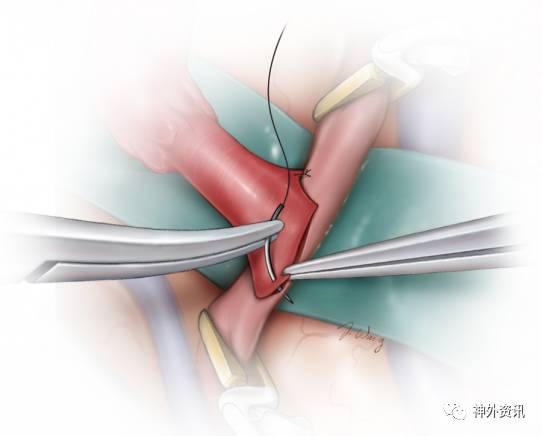

图9:演示吻合开始时的足跟、趾头对拢。使用9-0或者10-0的不可吸收线,先足跟部后趾头部将STA远端缝合至受血动脉的相应部位。缝针由外向内穿入STA,由内向外穿出受血的MCA分支。

最后,10-0的缝线间断缝合跟、趾两线之间的端-侧吻合口。

吻合口的侧边要么用2根缝线连续缝合,要么间断缝合8-10针。先吻合操作难度大的一侧,所以在闭合对侧之前可以从管腔内检查该侧的吻合情况。若采用连续缝合技术,使线圈保持松弛直至最末一针穿出以及肝素盐水再次冲洗,随后将其理顺依次抽紧并打结。

图10:应谨记缝针的穿行顺序:在供血动脉为由外向内,受血动脉则相反。如果采用的是间断缝合技术,完成最后一针之前冲洗管腔。注意保持缝针始终与动脉壁垂直以免线孔过大和戳裂管壁。受血动脉上大的破口不可被埋藏于缝线内否则会造成吻合口狭窄。

即使是很轻柔的动作,显微镊也容易扯断10-0的缝线,因此只有缝针可以被夹取。直视下穿入、穿出缝针,盲目操作可能会同时穿透受血动脉的两壁引起闭塞,必须予以禁止。

吻合结束后移除阻断夹,顺序是:先MCA远端,其次MCA近端,最终STA近端。若吻合口处有小的出血,使用可吸收性止血纱或其他止血材料轻轻压塞足以控制。

图11:STA-MCA搭桥时,采用连续缝合技术可能会有缝线在吻合口内侧缠结,间断缝合则可以降低该风险,但是完成吻合的时间要延长,个人倾向选择后者。切记供血动脉必须是没有张力和扭转存在。